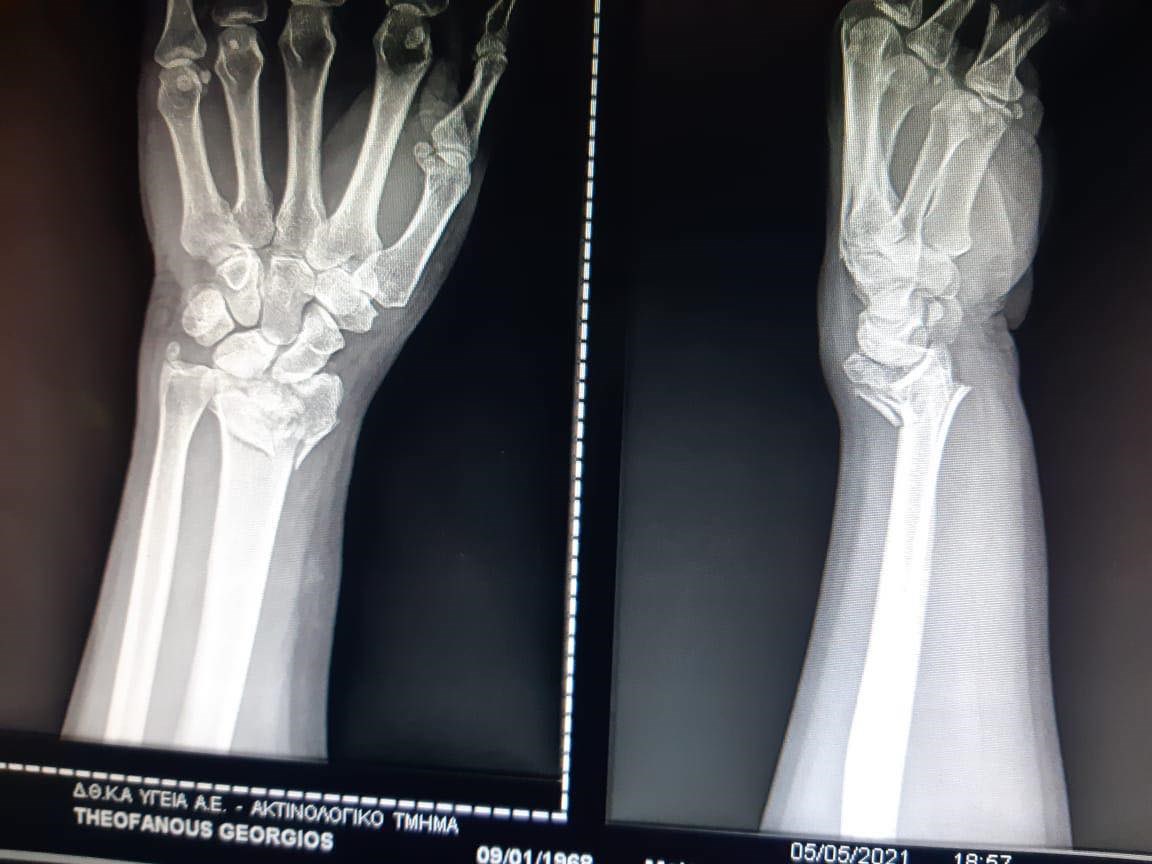

Ένα ατύχημα είχε χθες το μεσημέρι ο Γιώργος Θεοφάνους. Ο γνωστός συνθέτης μεταφέρθηκε στο νοσοκομείο, καθώς χτύπησε το χέρι του. Υποβλήθηκε σε χειρουργείο που κράτησε σχεδόν τρεις ώρες, καθώς κρίθηκε αναγκαίο να τοποθετηθούν λάμες και βίδες στο σημείο που τραυματίστηκε.

Το briefing.news δημοσίευσε δύο φωτογραφίες του Γιώργου Θεοφάνους από την ιδιωτική κλινική, στην οποία μεταφέρθηκε. Ο τραυματισμός του στο αριστερό του χέρι αναμένεται να τον κρατήσει μακριά από το πιάνο για τουλάχιστον δύο μήνες, κάτι που θα ανατρέψει και τα επαγγελματικά του σχέδια για το επόμενο χρονικό διάστημα.